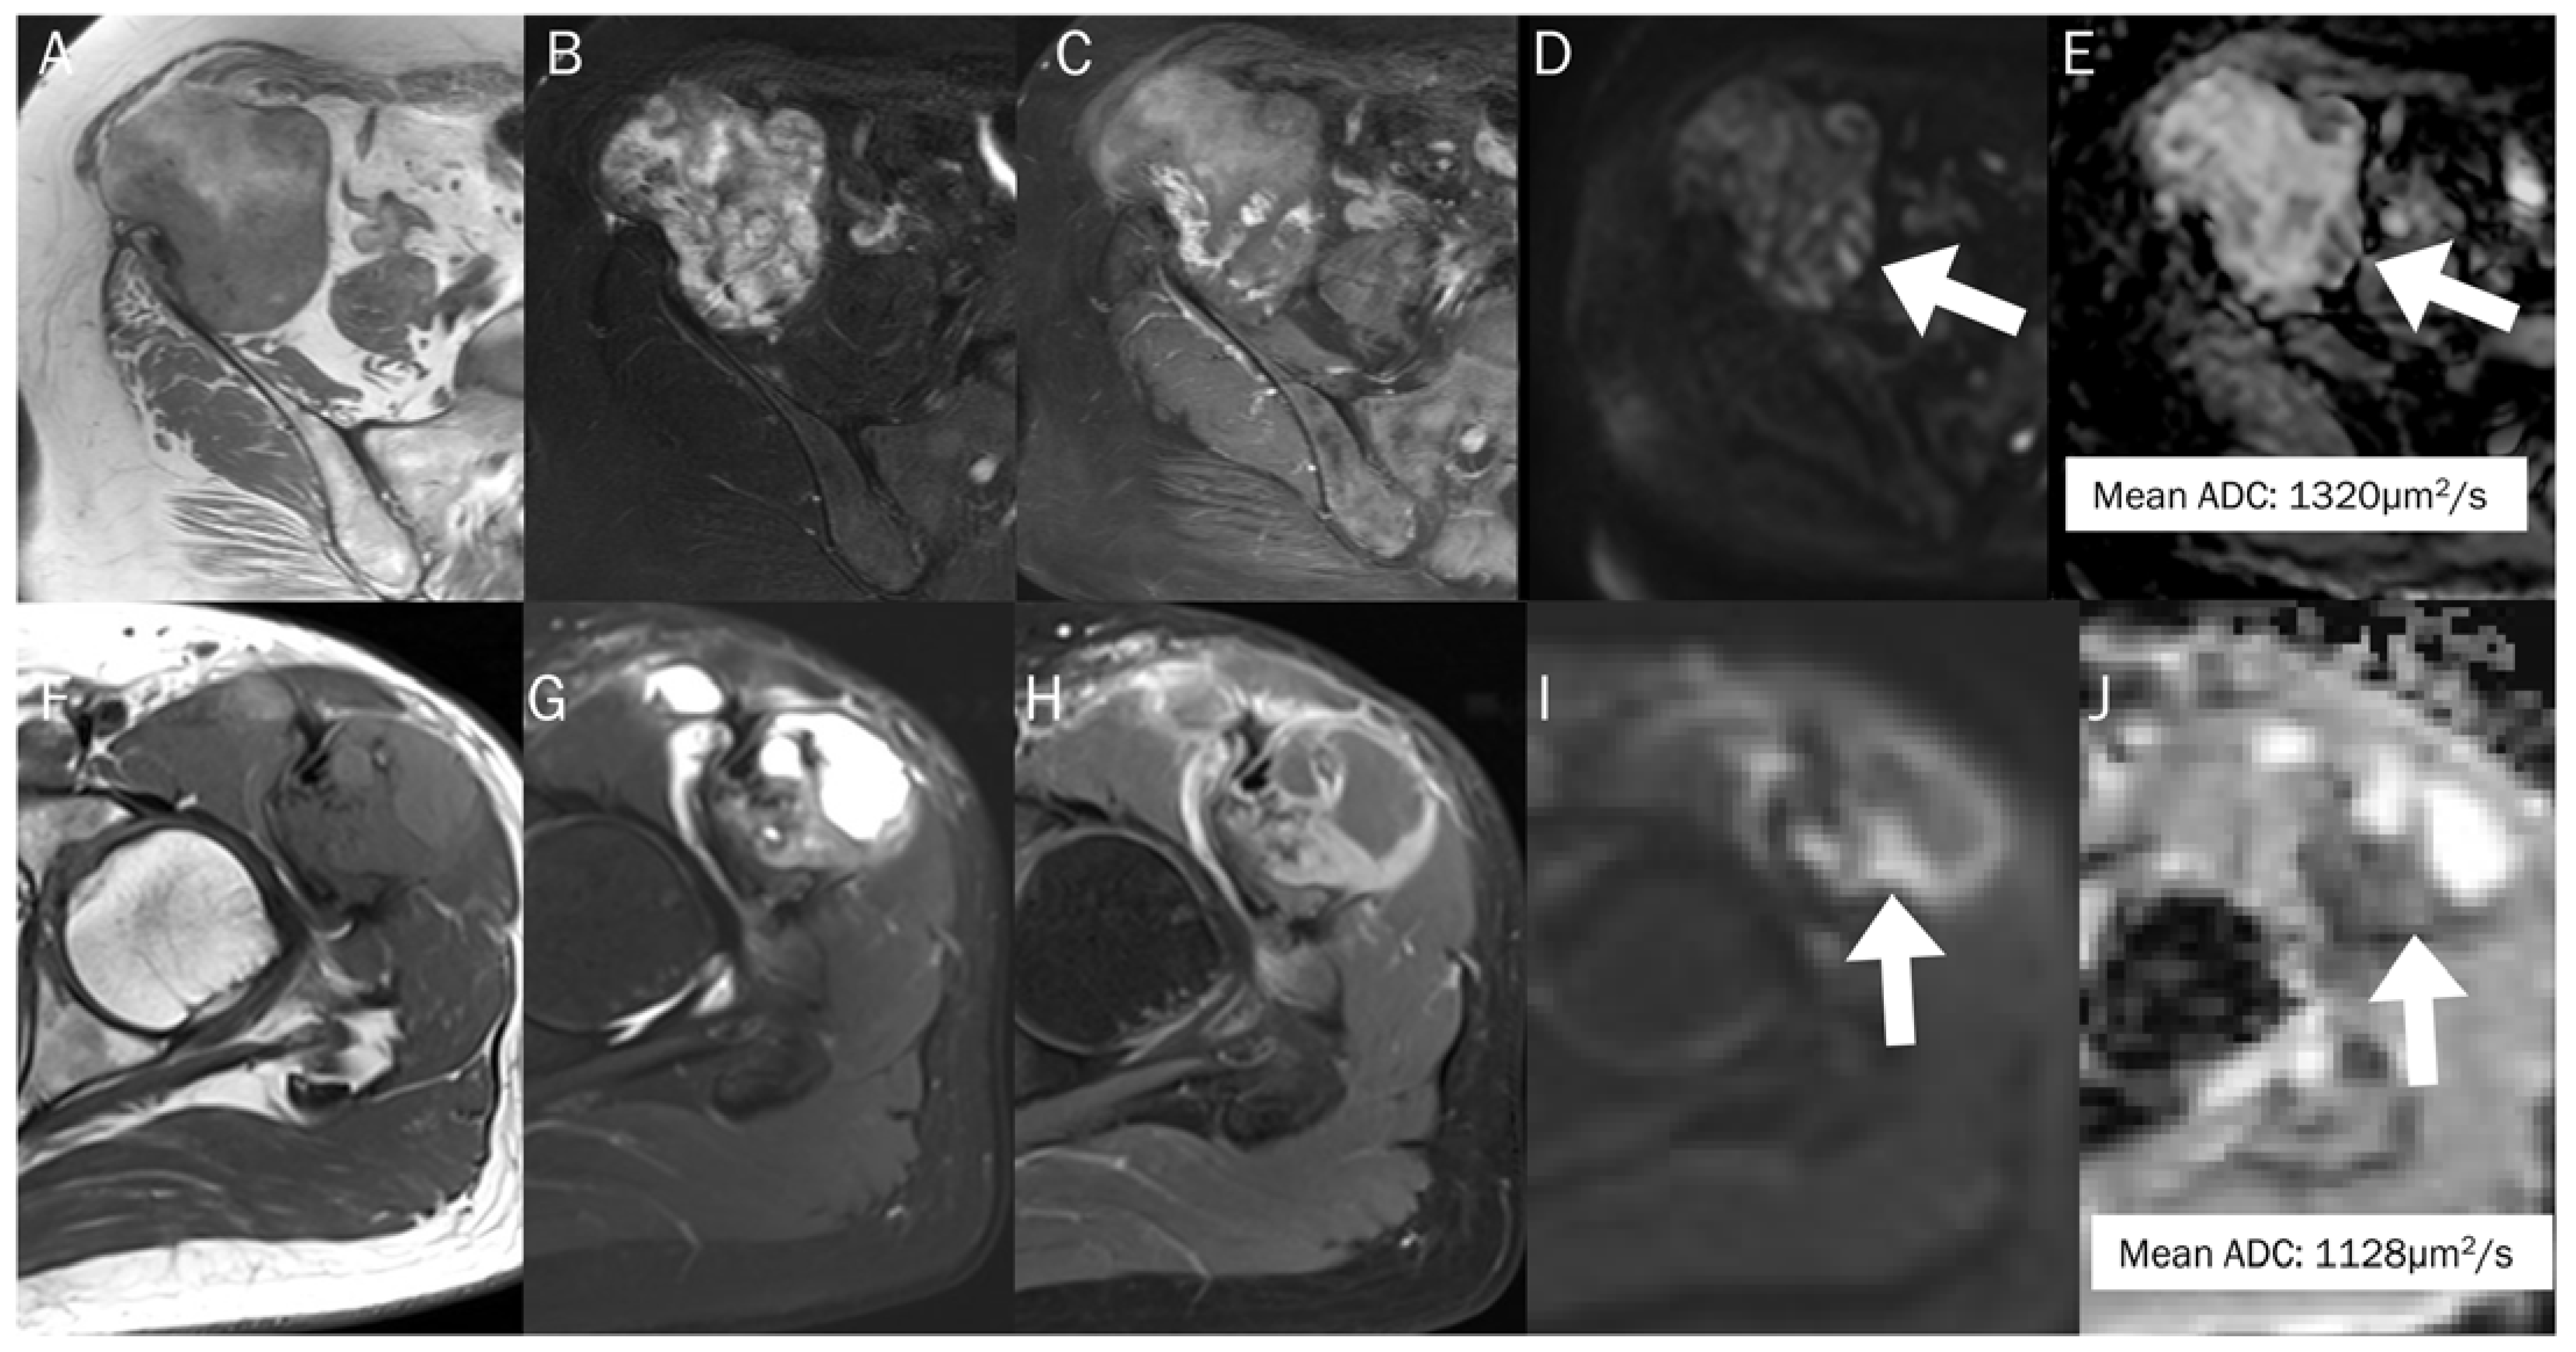

7.2. Hematoma

- Silvera, S.; Oppenheim, C.; Touzé, E.; Ducreux, D.; Page, P.; Domigo, V.; Mas, J.L.; Roux, F.X.; Frédy, D.; Meder, J.F. Spontaneous intracerebral hematoma on diffusion-weighted images: Influence of T2-shine-through and T2-blackout effects. AJNR Am. J. Neuroradiol. 2005, 26, 236–241. [Google Scholar]

| Stage | Component | Age | T1WI | T2WI | DWI | ADC Map |

|---|---|---|---|---|---|---|

| Hyperacute | Intracellular oxyhemoglobin | <6 h | Iso | Hyper | Hyper | Hypo |

| Acute | Intracellular deoxyhemoglobin | 6–72 h | Iso | Hypo | Hypo | Hypo |

| Early subacute | Intracellular methemoglobin | 3–7 d | Hyper | Hypo | Hypo | Hypo |

| Late subacute | Extracellular methemoglobin | 1–4 w | Hyper | Hyper | Hyper | Hypo-to-iso |

| Chronic | Hemosiderin | >1 m | Hypo | Hypo | Hypo | Hypo |